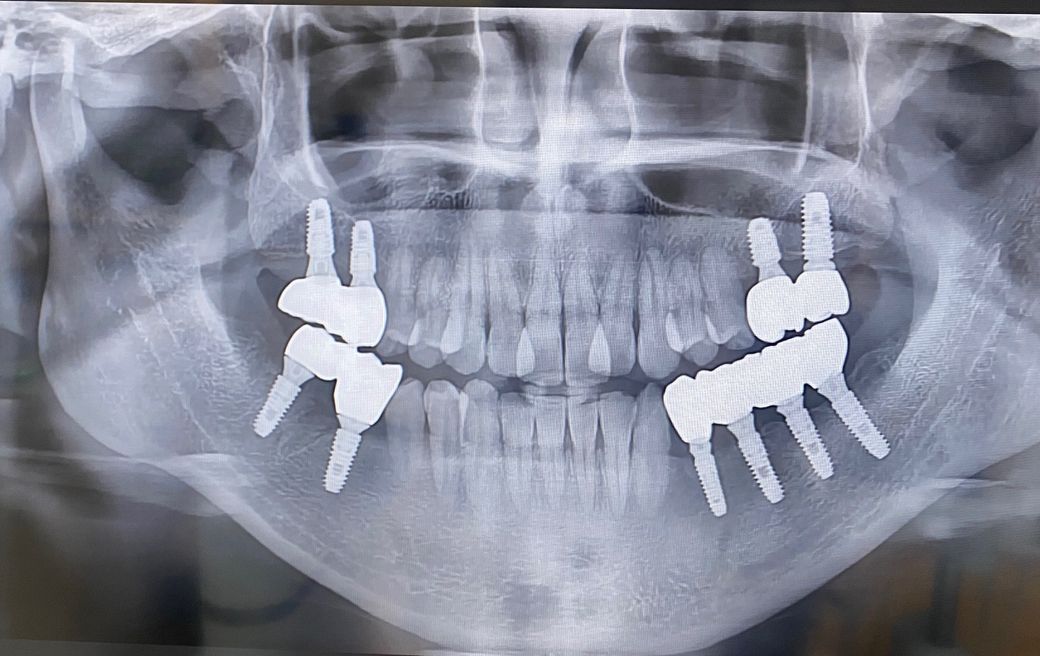

2016년에 식립하여 2017년 7월에 마무리해서 지금까지 사용하고 있습니다.

9년정도 사용하고있는데 코로나와 일적인 관계로 2025년에 치과를 방문하여 x-ray사진을 찍었습니다. 치과에 정기적으로 방문하지 않아서 스케일링도 올해들어 했습니다. ㅠ

전체적으로 잇몸뼈 손실이 있는지 그리고 갈 수로 잇몸이 내려앉아 사진처럼 지대주가 보이고, 잇몸과 치아사이에 블랙트라이앵글도 더 크게 생겼습니다. 지대주가.노출되면 더 주위염에 노출될 위험이 큰지? 아니면 청소가.더 잘되서 더 유리한지? ㅜ 알려주세요. ㅜ

(아래 사진은 2017년 7월 사진)

(아래사진은 2025년4월 사진)

사진으로 봤을 경우에 임플란트를 둘러 싸고 있는 치조골의 양은 잘 유지가 되고 있는것으로 보입니다.

잇몸의 염증이 없다면 붓기가 가라않으면서 블랙트라이 앵글이 생기는 경우도 있습니다.

임플란트 주변을 꼼꼼이 양치질하고 치간칫솔을 사용해 보세요.

워터픽을 사용하면 임플란트 주위를 더 깨끗하게 관리할수 있습니다.